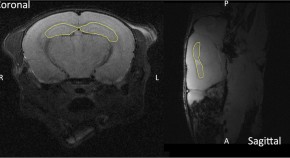

Melanocortin 4 receptors (MC4Rs) are critical to the promotion of homeostatic satiety. The authors established paraventricular hypothalamus (PVH) MC4R-expressing neurons as a functional target for orexigenic arcuate nucleus agouti-related peptide–expressing neurons and identify an explicit PVH MC4R-expressing neuron to lateral parabrachial nucleus satiety-promoting circuit, the activation of which encodes positive valence in calorically depleted mice.